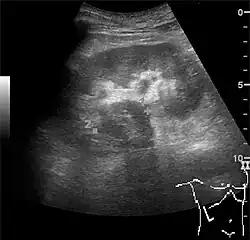

With US, larger stones (>5–7 mm) within the kidney, i.e., in the calyces, the pelvis and the pyeloureteric junction, can be differentiated, especially in the cases with accompanying hydronephrosis (Figure 18 and Figure 19). Hyperechoic stones are seen with accompanying posterior shadowing. Additional twinkling artifacts below the stone can often be seen using Doppler US. Large stones filling the entire collecting system are called coral stones or staghorn calculi and are easily visualized with US (Figure 20). Stones in the ureters are usually not visualized with US due to the air-filled intestines obscuring the insonation window. However, ureteral stones near the ostium can be visualized with a scan position over the bladder. An exam of the ureteric orifices and the excretion of urine to the bladder can be performed by inspecting the ureteric jets in the bladder with color Doppler US.

Figure 20. Staghorn calculi filling the entire collecting system and creating pronounced shadowing.[1] -